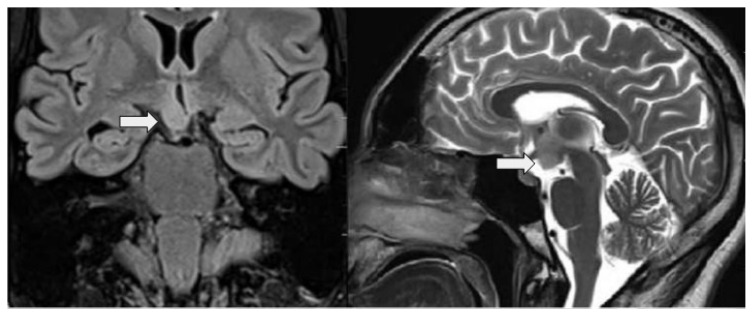

回旋性癫痫发作(GS)是一种罕见的癫痫发作类型,其特征是身体绕垂直轴旋转≥180°。虽然在各种癫痫综合征中都有回旋性癫痫发作的记录,但与下丘脑仓鼠神经瘤(HH)相关的回旋性癫痫发作此前尚未见报道。本病例报告首次记录了一名下丘脑火腿肠瘤(HH)患者出现 GS 的病例。患者是一名 25 岁的女性,自孩提时代起就有反复发作的病史,最初表现为凝胶样发作,以不适当的大笑为特征,随后症状演变为右侧眼球后凸和右侧回旋性发作。尽管服用了多种抗癫痫药物,但癫痫仍持续发作。神经影像学检查显示,患者右侧下丘脑区域有一处 HH。多指畸形的出现促使患者考虑帕利斯特-霍尔综合征(Pallister Hall Syndrome,PHS)。PHS 是一种常染色体显性遗传病,与 GLI3 基因突变有关。虽然该病例不具备PHS的某些特征,但凝胶痉挛和回旋性癫痫发作的出现表明下丘脑是病变部位,尽管脑电图结果并不确定。该报告强调了GS与HH的新关联,并强调了在HH和多指畸形患者出现凝胶样和回旋性癫痫发作时考虑PHS的重要性。了解HH中的GS可能有助于深入了解更广泛的下丘脑病变相关癫痫现象。

Gyratory seizures (GS) are a rare seizure type characterized by body rotation of ≥180° around its vertical axis. While GS have been documented in various epileptic syndromes, their occurrence in association with hypothalamic hamartomas (HH) has not been reported previously. This case report introduces the first documented instance of GS in a patient with a HH, a non-neoplastic tumor originating from the tuber cinereum. The patient, a 25-year-old female, with a history of recurrent seizures since childhood, initially presented with gelastic seizures, marked by inappropriate laughter, and subsequent evolution of symptoms including right oculocephalic version and gyratory seizures to the right side. Despite multiple antiepileptic medications, seizures persisted. Neuroimaging revealed a HH in the right hypothalamic region. The presence of polydactyly prompted consideration of Pallister Hall syndrome (PHS). PHS is an autosomal dominant condition linked to GLI3 gene mutations. While some features of PHS were absent in this case, the presence of both gelastic and gyratory seizures indicated the hypothalamus as the lesion site, despite inconclusive electroencephalogram findings. This report underscores the novel association of GS with HH and highlights the importance of considering PHS in patients with HH and polydactyly presenting with gelastic and gyratory seizures. Understanding GS in HH may offer insights into broader hypothalamic lesion-related epileptic phenomena.